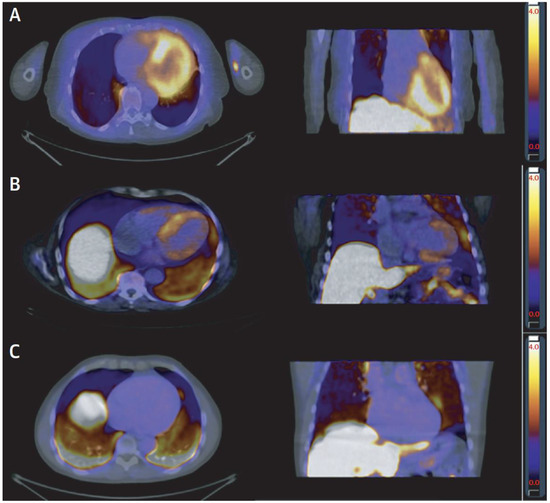

| Nuclear Perfusion Imaging | Assessment of myocardial perfusion (coronary or microvascular disease); assessment of amyloidosis with specific tracers; sarcoidosis | PET is gold standard for myocardial perfusion; identification of perfusion/metabolism mismatch, as in hibernating myocardium; high accuracy for amyloidosis and sarcoidosis; DPD imaging (planar/SPECT) is sensitive for cardiac ATTR amyloidosis | PET limited to centers with cyclotron; radiation exposure |